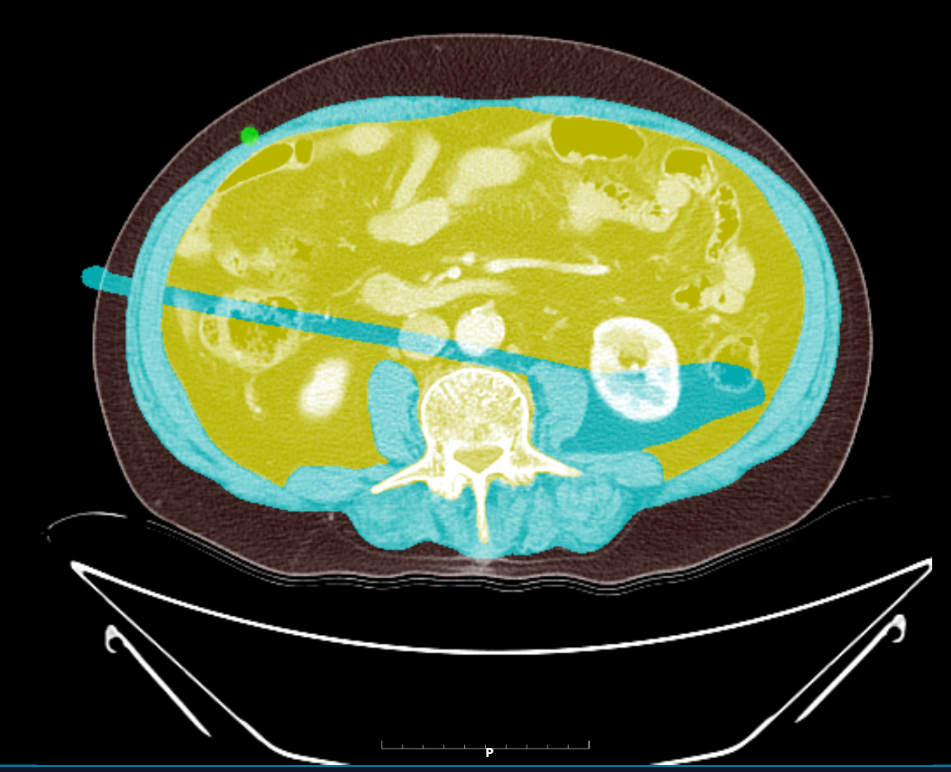

근육과 지방 자동 분석

근육 지방 분석

결과 확인 및 수정 가능

결과 수정

✏️

수동 수정 가능

AI가 혹시 놓친 부분도 웹에서 직접 수정 가능! 완벽한 결과를 보장합니다.